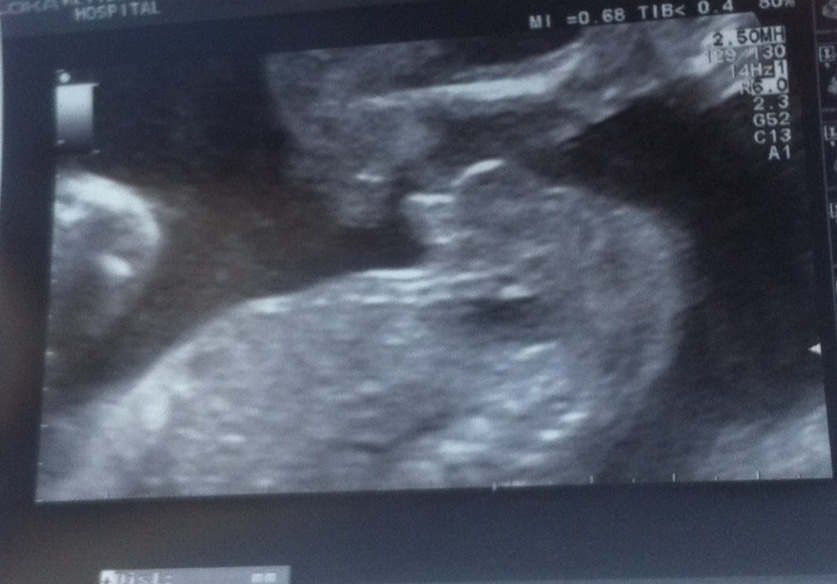

Thank you gender dreaming. My sway worked.Attachment 16386 Here are my ultrasound pics that are confirmed boy :).

20week 4 days